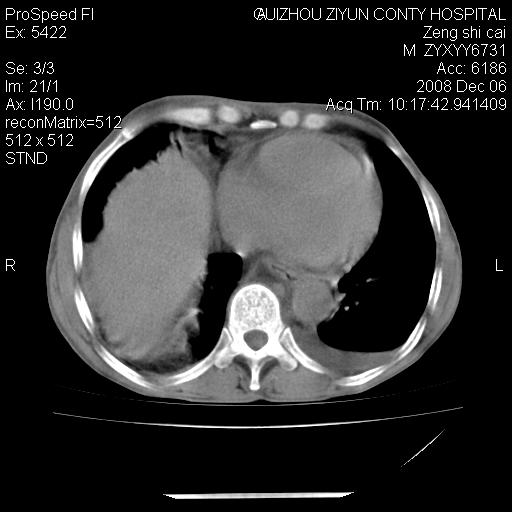

标题: CT16961:M、71岁,咳嗽半年,无血痰;胸片示右肺占位。 [打印本页]

标题: CT16961:M、71岁,咳嗽半年,无血痰;胸片示右肺占位。

升结肠癌伴腹膜后淋巴结转移

右肺癌并纵隔淋巴转移,腹膜后转移可能性大,两侧胸腔积液

1)考虑右肺上叶纵隔型肺癌伴纵隔淋巴结转移。2)心包积液,双侧胸腔积液。

右肺纵隔型肺癌伴纵隔淋巴结及胸膜转移